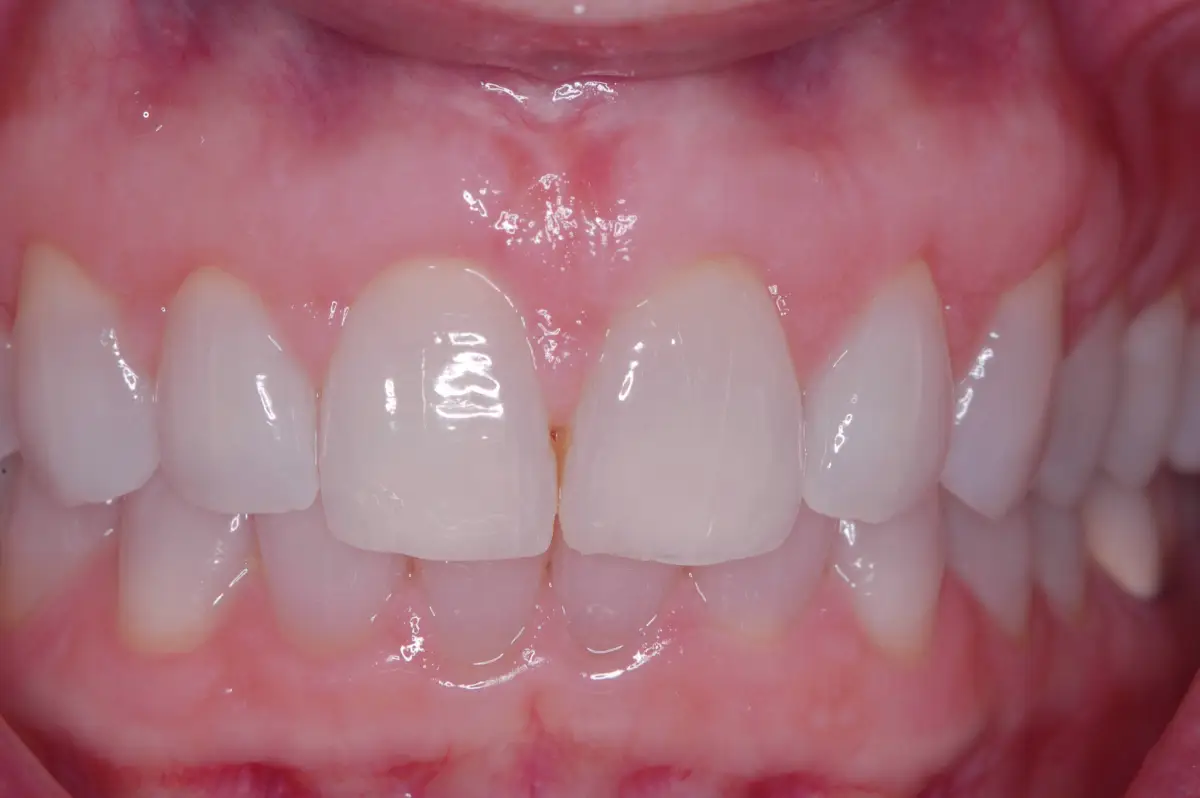

Frenectomy

before

after